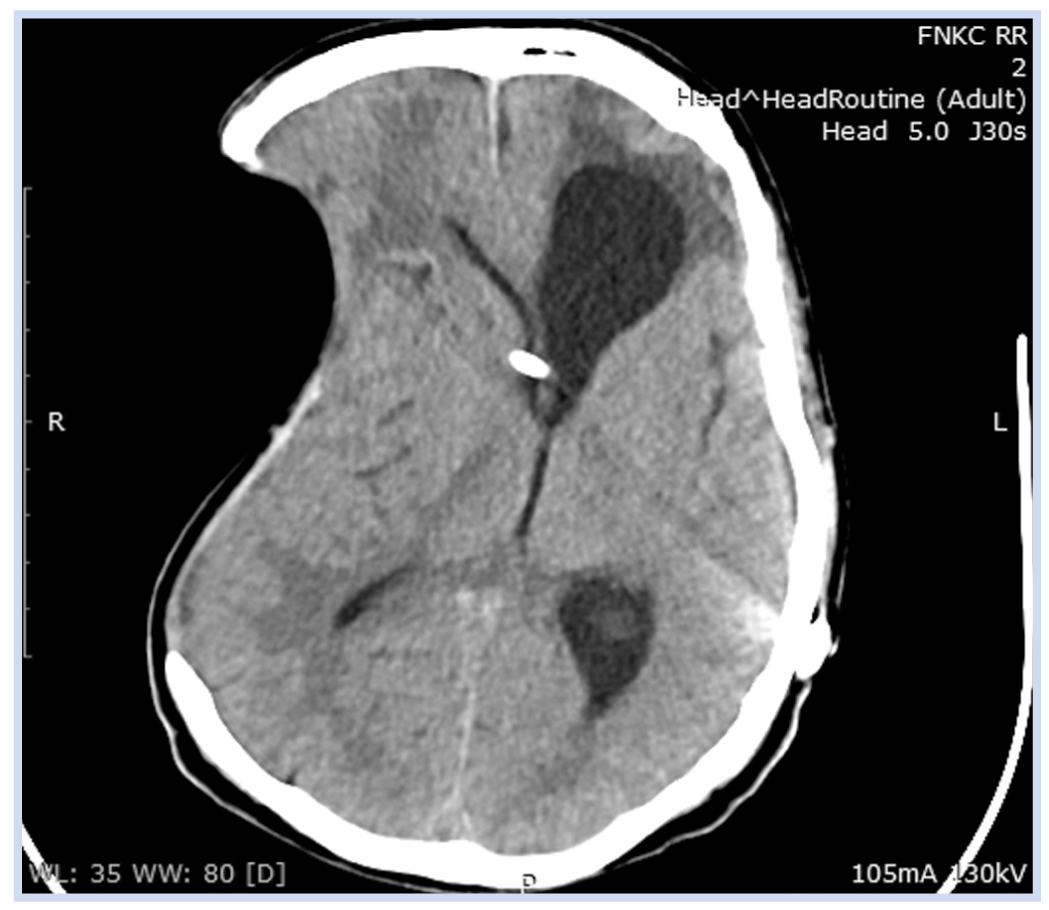

По результатам спиральной КТ при поступлении отмечалось наличие гигантского посттрепанационного дефекта костей свода черепа в правой лобно-теменно-височной области (рис. 2).

Рис. 2. Пациент К., 50 лет, с посттравматической гидроцефалией и посттрепанационным дефектом костей свода черепа: спиральная компьютерная томограмма в виде 3D-реконструкции от 30.03.2020

Примечание. Наличие гигантского посттрепанационного дефекта костей свода черепа в правой лобно-теменно-височной области.